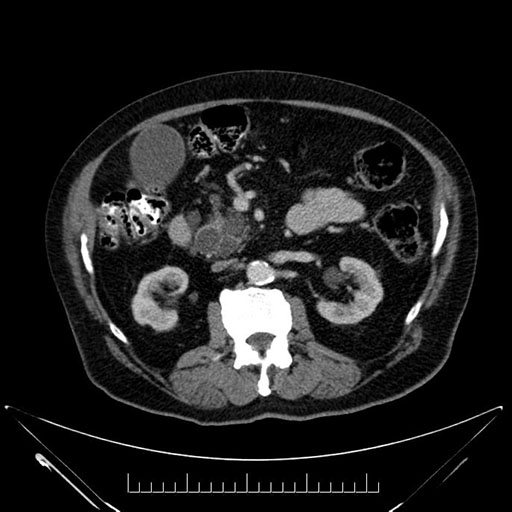

Imaging Analysis

Look through the patient's CT scan to identify any areas of concern for the necessary procedure.

Based on your CT findings, which issue(s) would give reason for "planned slowing down moment(s)" in this case?